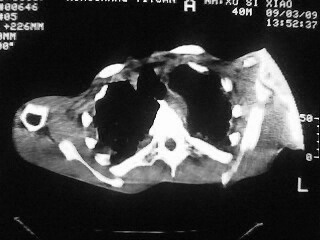

m,45,咳嗽、气憋月余。先天性畸形

1)两肺上叶继发性肺结核,部分肺间质纤维化。2)慢性支气管炎。3)肺气肿,两上肺多发性肺大泡。4)右侧胸膜增厚可能。5)脊柱上胸段畸形。

考虑:1)两肺上叶继发性肺结核,部分肺间质纤维化。2)慢支肺气肿并两上肺多发性肺大泡。3)右侧胸膜增厚可能。5)脊柱上胸段畸形。

补充一下,病人有强直性脊柱炎十多年

慢支炎、肺气肿、间质纤维化,双肺结核,脊柱侧弯

脊柱侧弯后突畸形,1)两肺上叶继发性肺结核,部分肺间质纤维化。2)慢支肺气肿并两上肺多发性肺大泡。3)右侧胸膜增厚可能。5